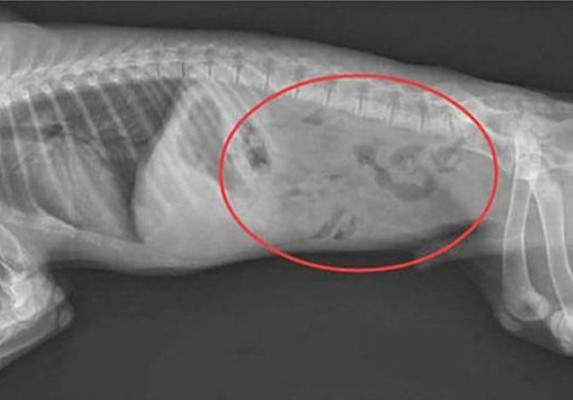

铲屎官观察了几天觉得不对劲 , 便赶忙带着二哈去医院进行检查了 , 拍了片子后铲屎官顿时不知道该说啥了 , 只能说该!

原来二哈之所以吃不下东西 , 是因为肚子里有不少好东西呢 , 都是铲屎官的戒指、耳环、项链等首饰 , 你说这不是私藏小金库嘛 , 到底想干什么?携款潜逃呀 。 这么一想 , 难怪铲屎官觉得自己的东西总是找不到了呢 , 原来都到了家贼的肚子里呀 , 想想都后怕 。

兽医小明看到这些从肚子里取出来的首饰也是哭笑不得 , 大家一定要将这些东西收好呀 , 贵不贵重是一回事 , 万一狗狗不小心吞到了肚子里 , 还得手术取出来了 , 这对狗狗的身体健康也是不利的 , 再说了手术费用也不低呀 , 这不是花钱找罪受嘛 。